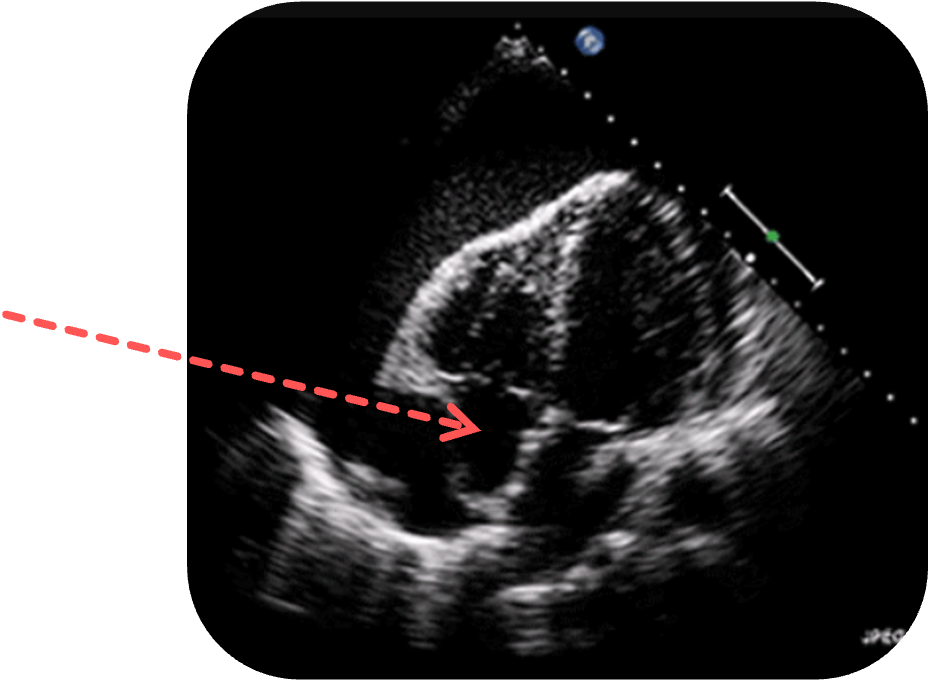

Perikardtamponade

Wie beim Perikarderguss zeigt sich sonographisch eine anechogene oder echoarme Flüssigkeitsansammlung im Perikardraum, die das Herz zirkulär umgibt.

Im Gegensatz zum einfachen Erguss finden sich bei der Perikardtamponade

Eine relevante Perikardtamponade

Paradoxe Septumbewegung:

Während der Inspiration

Die Folge ist ein sogenannter Pulsus